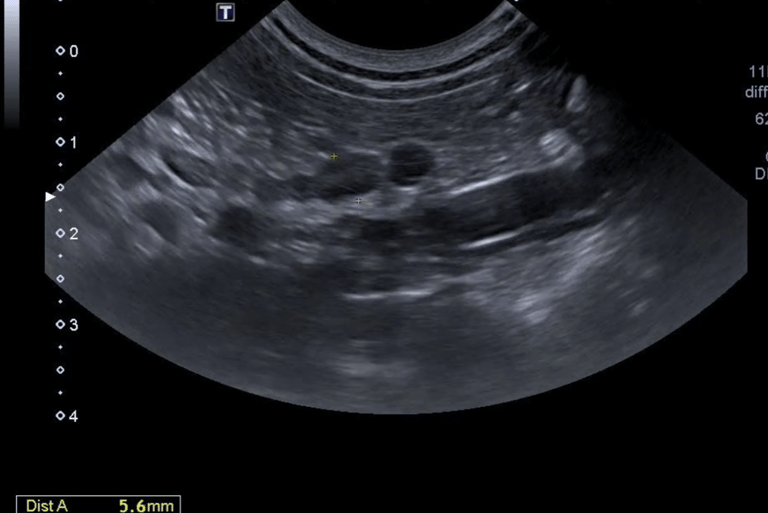

10 - De quel organe s'agit-il ?

A - Le Foie

B - La Rate

C - La Prostate

D - Le Jéjunum

E - Le Pancréas

11 - Sur cette même image échographique que pouvez-vous dire ?

A - J'observe la présence d'une hyperéchogénicité du parenchyme

B - Je n'observe aucune anomalie

C - J'observe la présence d'une hypoéchogénicité du parenchyme

D - J'observe la présence d'un effet de masse

12 - De quel organe s'agit-il ?

Question 10 : Réponse B

Question 11 : Réponse B